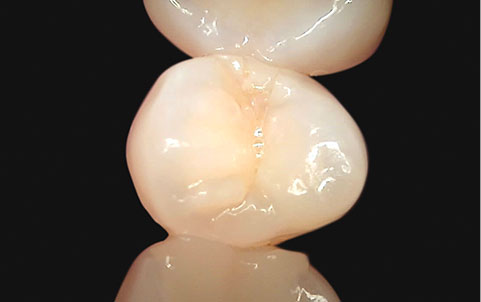

05

荧光分析, 用视频精密检查

Qraypen C

用荧光装备能确认, 在自然光下难以识别的

牙菌斑, 牙结石, 蛀牙, 牙齿裂纹等

可同时进行一般拍摄和光学拍摄, 比较牙齿的现状 .[ 诊断蛀牙装备 (Qraypen C) ]

医疗器械2等级-光合式蛀牙诊断装置,

使用与难以接触到的牙齿面拍摄 通过一次荧光拍摄能确认牙齿的裂纹, 腐蚀, 牙菌斑等

除了能提前确认外, 修复牙齿的后期管理, 矫正患者的

蛀牙及牙菌斑管理, 蛀牙检查,

预防蛀牙等都能确认并改善 .

一般拍摄

光学拍摄 -